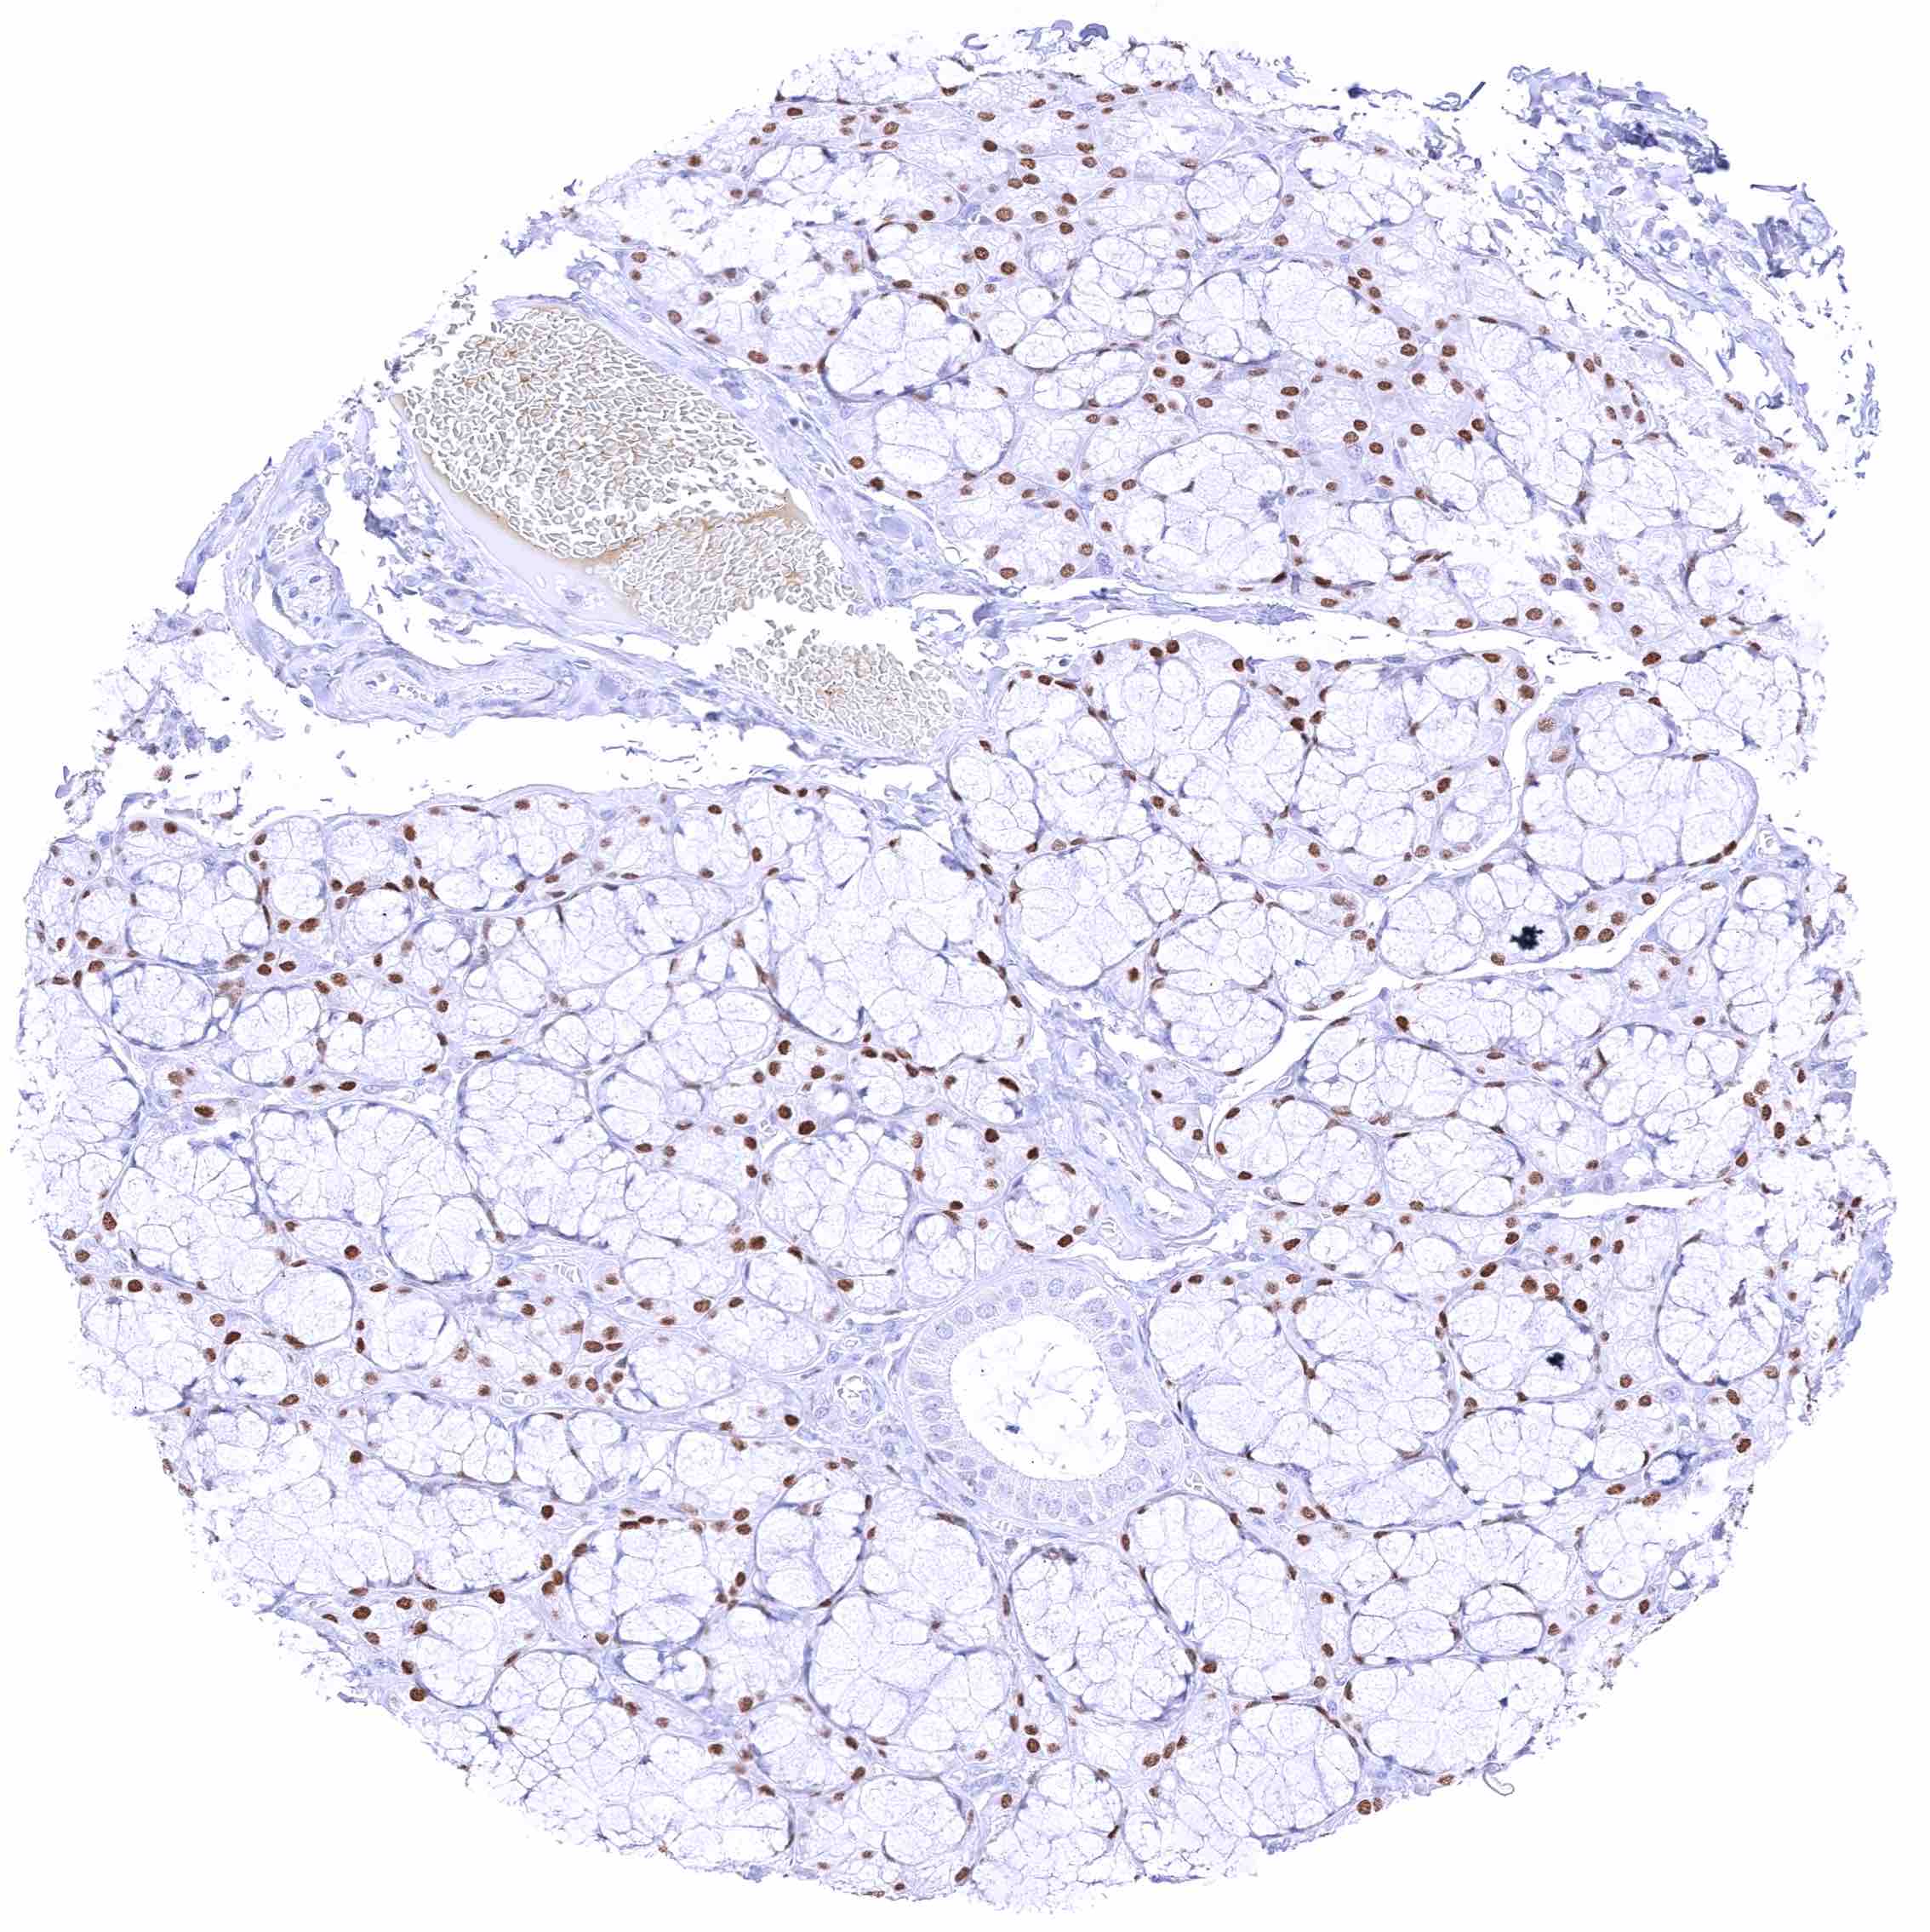

Parotid gland – Weak to moderate, nuclear GATA3 positivity of glandular cells.

Sublingual gland – Moderate to strong, nuclear GATA3 positivity of glandular cells.

Submandibular gland – Moderate to strong, nuclear GATA3 positivity of glandular cells.